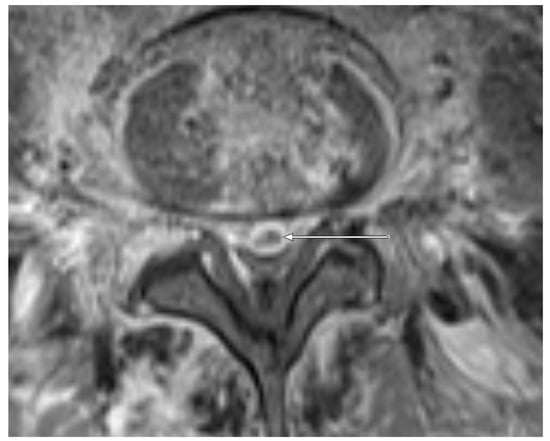

Figure 2. Transversal T1 weighted, fat-saturated, contrast-enhanced image of the lumbar spine level L5/L6 in a 52-year old patient. An epidural abscess is present (arrow). The detected pathogen after CT-guided biopsy was E. coli.

Figure 3. Sagittal T1 weighted, fat-saturated, contrast-enhanced image of the lumbar spine level L5-S1 in the same patient as shown in Figure 2. The epidural abscess in the spinal canal is marked with an arrow.

MRI: PA (Figure 1) was observed in 7/11 (63.6%) patients with positive microbiology compared to only 7/29 samples (24.1%) with negative microbiology. EA (Figure 2 and Figure 3) was present in 3/11 (27.3%) patients with positive microbiology but only in 2/29 (6.9%) samples with negative microbiology. EA was also present in all patients featuring PA.